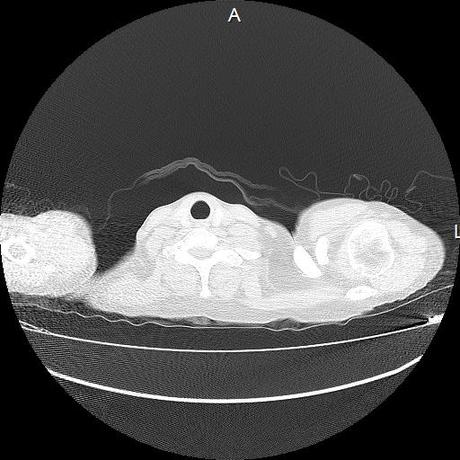

Se realiza volumen de tórax en fase simple, desde los opérculos torácicos hasta los hemidiafragmas, observándose:

Estructuras óseas sin evidencia de lesiones líticas, blásticas ni trazos de fractura. A nivel de cuerpo vertebral de T10 se observa nódulo de Schmorl que distorsiona el borde superior del cuerpo vertebral.

El parénquima pulmonar con areas parcheadas difusas en vidrio despulido combinadas con otras areas hipodensas de baja atenuación debidas a atrapamiento aéreo y engrosamiento intersticial y zonas de fibrosis de predominio en lóbulos medios e inferiores de ambos pulmones.